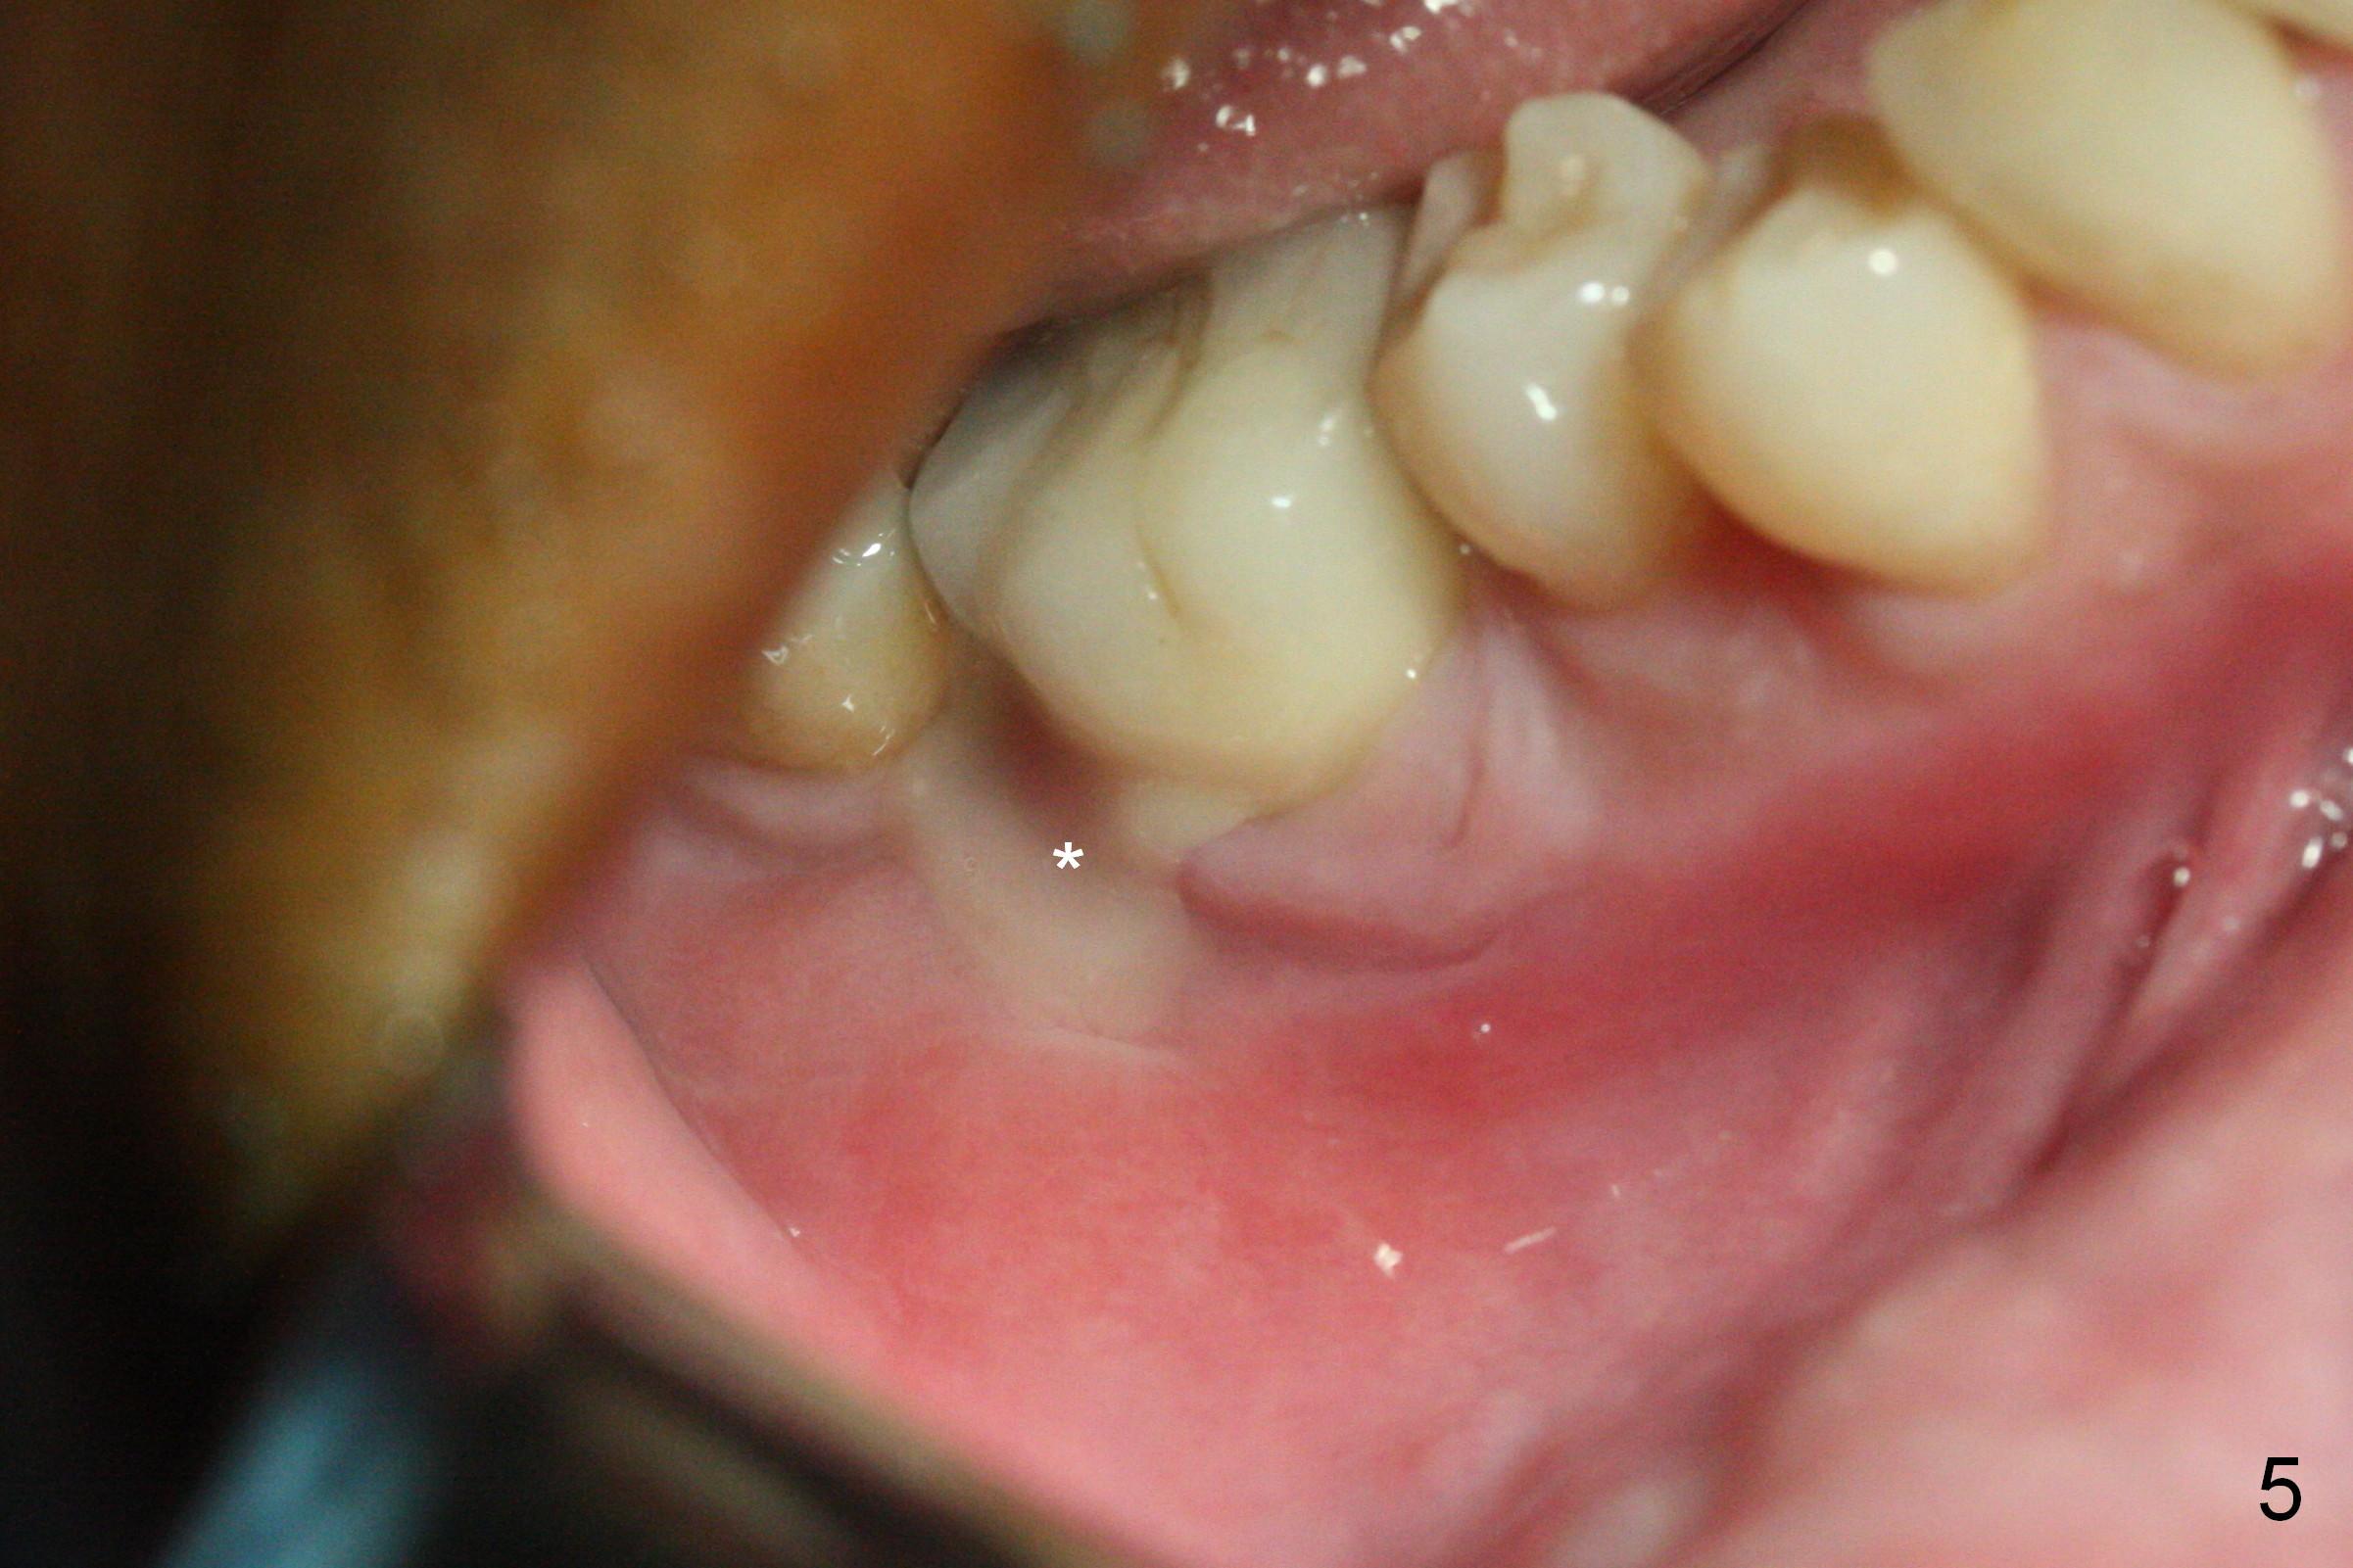

A 49-year-old man develops acute abscess of the lower right quadrant (Fig.3-5) secondary to periimplantitis at #30 (Fig.1,2,6). The latter is probably due to buccal placement (Fig.6 (*: buccal plate)). After removal of the infected implant, an osteotomy is established as lingual as possible using single drill modality (Fig.7 (4.3 mm Magic Drill after 1.6 mm pilot drill and Marking Bur, then Final Drill). With the single drill, the osteotomy does not shift buccally in spite of the lower buccal plate. A 5x9 mm IBS implant is placed lingually as planned (Fig.8 (>40 Ncm)), followed by an angled abutment (5 mm x 15° (4 mm)) (Fig.9 A). The buccal gap is filled with autogenous bone, allograft (.5-1.5 mm) and Osteogen (Fig.10 *), covered by resorbable and non-resorbable membranes. After suturing, periodontal dressing is applied.